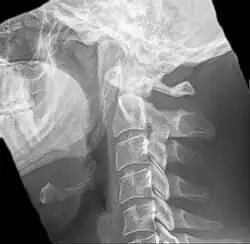

Radiograph, lateral view showing elongated stylohyoid process and stylohyoid ligament ossification -

Radiograph, lateral view showing joint-like formation in ossified stylohyoid ligament -